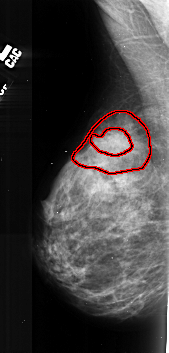

A_1027_1.LEFT_MLO

LEFT_MLO LINES 5281 PIXELS_PER_LINE 2521 BITS_PER_PIXEL 16 RESOLUTION 42 OVERLAY

FILE: A_1027_1.LEFT_MLO.OVERLAY

TOTAL_ABNORMALITIES 1

ABNORMALITY 1

LESION_TYPE MASS SHAPE LOBULATED MARGINS SPICULATED

ASSESSMENT 5

SUBTLETY 4

PATHOLOGY MALIGNANT

TOTAL_OUTLINES 2

BOUNDARY

CORE